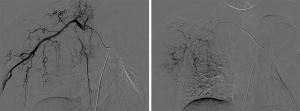

The patient declined surgery and systemic chemotherapy. She underwent CT-guided percutaneous co-ablation (Co-A, distinguished with CA) in our operating room (Figure 3). The Co-A procedure was performed by using a nitrogen-ethanol-based HJY CHS 800001 Co-ablation system (Hygea Medical Technology Co., Beijing, China). Liquid nitrogen was delivered into the probe to decrease the probe temperature to as low as −196 ℃ as it transitioned from a liquid to a gas phase. In the active thawing phase, ethanol was circulated in the tip of the needle, increasing the probe temperature to as high as 80 ℃ upon transition from a gas to a liquid phase in the probe. The flow of the nitrogen and ethanol was controlled by a computer-modulated device within the unit. In this study, we used a type of 14 G co-probe that allows an iceball formation of (51.2±2.3) mm × (39.3±1.7) mm at −196 ℃ in vitro. The co-probe was 1.98 mm in outer diameter and 140 mm in length. We ablated 4 sites using 2 14 G co-probes. We performed 4 freeze-thaw cycles to fully destroy the base as well as the body of the tumor, with the specific protocols of 5 minutes of freezing/3 minutes of thawing (2 cycles), and 10 minutes of freezing/3 minutes of thawing (2 cycles). We carried out 2 freeze-thaw cycles consecutively. After Co-A of one site was completed, the co-probe was adjusted to ablate the second site. During the Co-A process, we did not implement any skin protection measures because our goal was to achieve complete necrosis at the base of the tumor and then detachment through Co-A. Repeat plain CT after the Co-A showed a significant decrease in the mass density. The procedure was performed under local anesthesia and the patient cooperated well. It also acted as an analgesic, which was a significant advantage of Co-A over heat-based ablations. Subsequently, the patient underwent 3 cycles of catheter-preserving local infusion chemotherapy of the right subclavian artery, with the following regimen: 40 mg piroxicam and 400 mg cyclophosphamide (Figures 4,5).